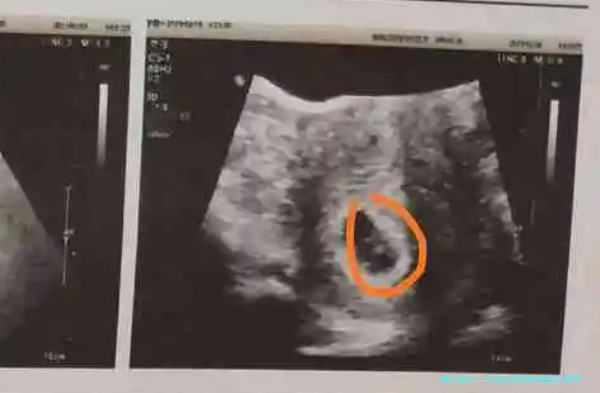

1、检查费用,在进入试管婴儿周期术前,夫妻两边都要进行身体检查,了解自我情况为了便于确定试管方,检查实质囊括中国去泰国做试管费用:血液检查、性激素六个项目检查、B超检查及精液检测等。

在进行试管婴儿时,有些患者的排卵功能相比差,因这需要要多注射一些药物促排卵,卵泡的监测很重要,需要做多次B超检查,利便医生会根据卵泡监测的情况,对药物进行调节。